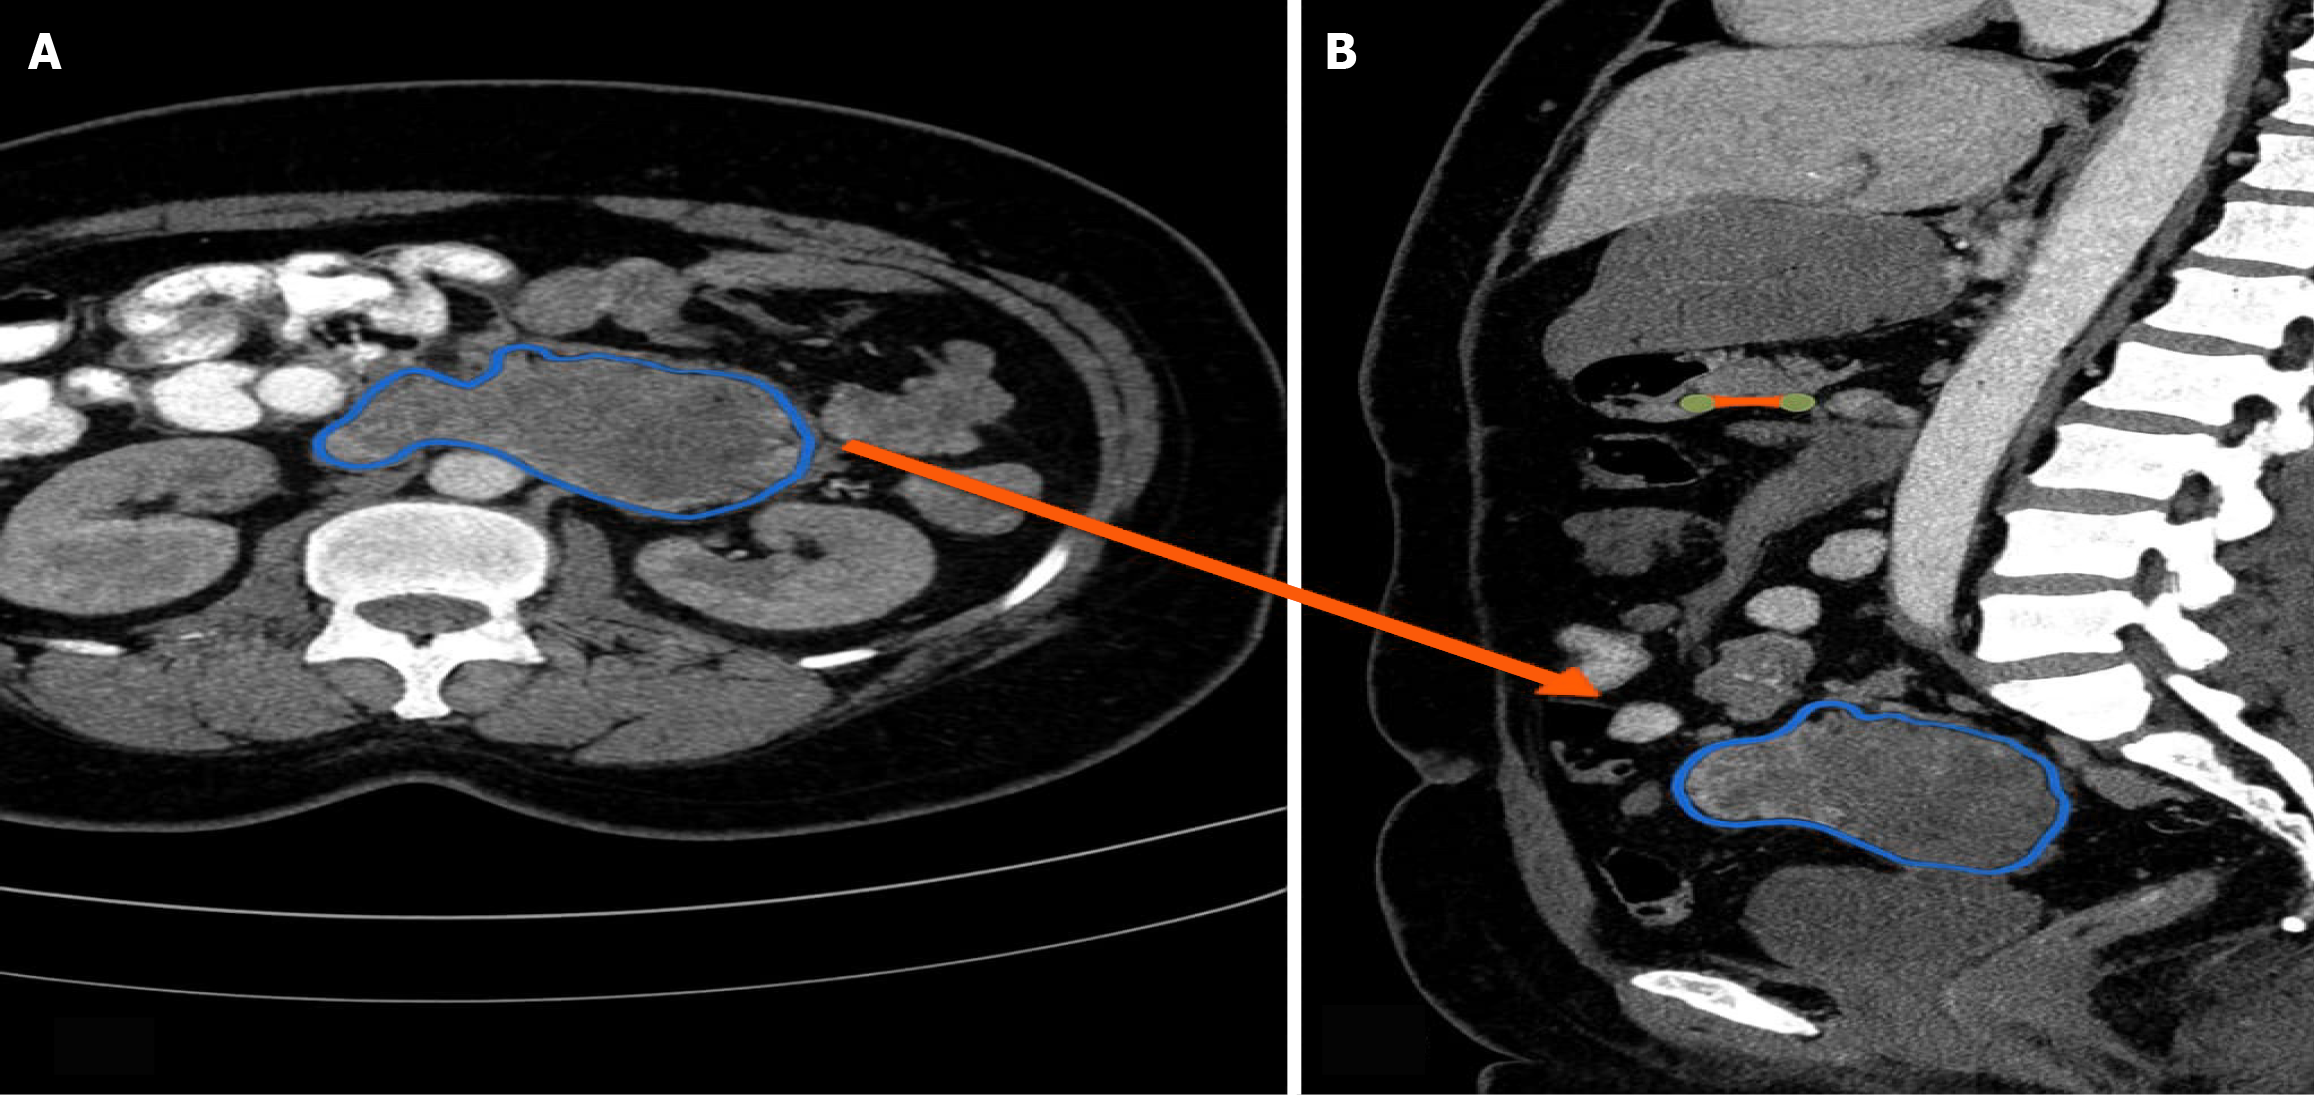

Figure 1 Computed tomography.

A: Coronal section showing large duodenal tumor; B: Sagittal section showing similar findings (blue highlight, orange arrow).